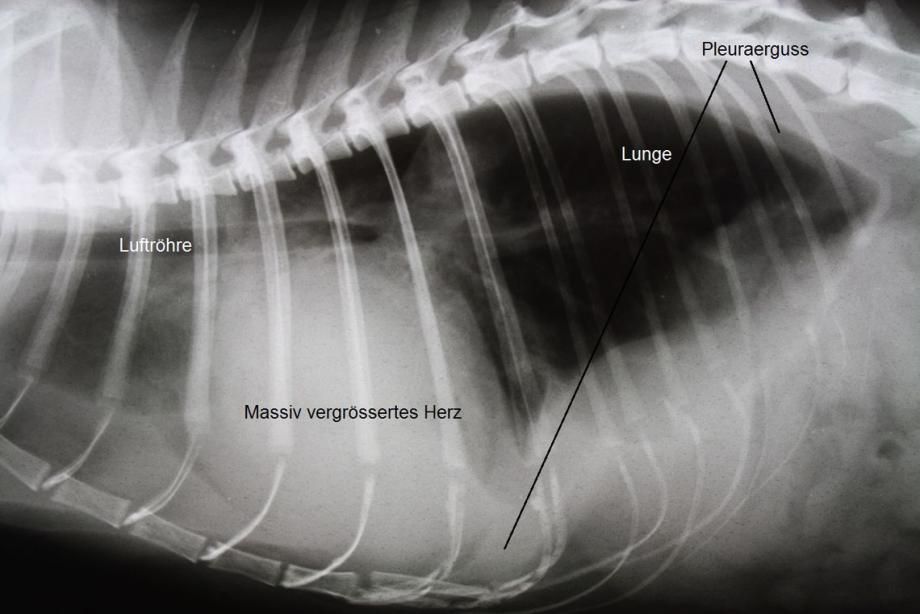

Alle Befunde weisen darauf hin, dass Schnurrli eine Blockade der Schenkelarterien durch ein Blutgerinnsel aufweist (Sattelthrombus) - meist ist dieses Problem durch eine primäre Herzerkrankung mit folgender Bildung von Blutgerinnseln bedingt. Ein Röntgenbild bestätigt, dass das Herz der Katze enorm gross ist und sich im Brustkorb ein Erguss gebildet hat - beides typische Befunde bei Herzproblemen.